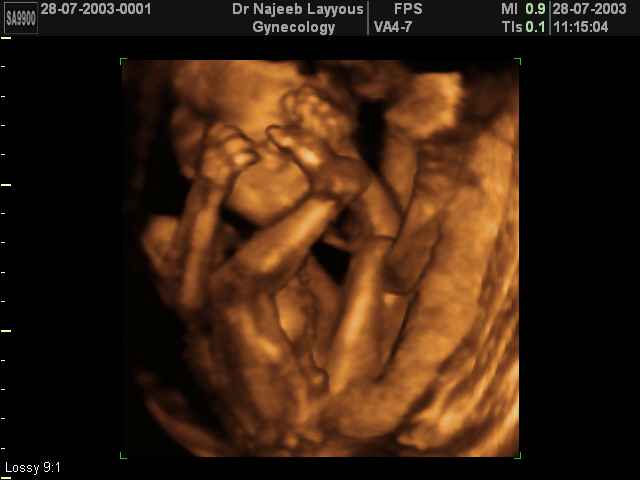

3D second trimestre échographie Photos de numérisation - deuxième partie de la grossesse | Dr N Layyous

3D second trimestre échographie Photos de numérisation - deuxième partie de la grossesse